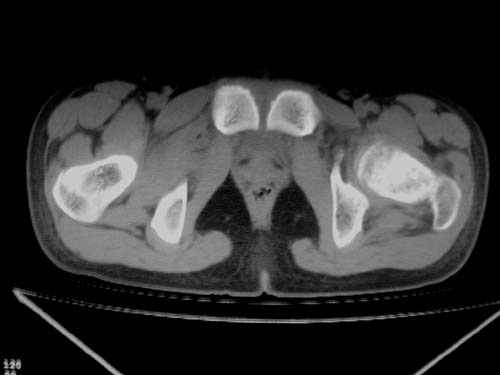

标题: CT19608:女12岁,左髋部疼痛,无发热病史 [打印本页]

标题: CT19608:女12岁,左髋部疼痛,无发热病史

左股骨干增粗,磨玻璃样改变——考虑骨纤维异常增殖症!

左股骨干增粗,磨玻璃样改变——考虑骨纤维异常增殖症!骨化性纤维瘤?